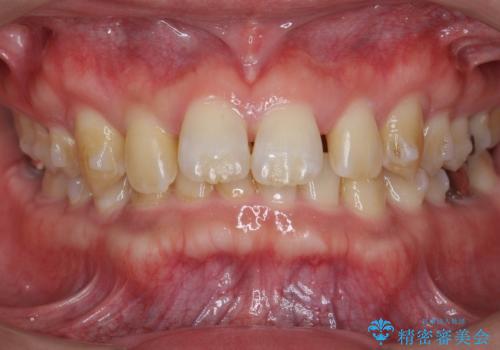

ディープバイトのマウスピース矯正

- 飛び出してしまい、隙間のある前歯をきれいに並べたい、と矯正治療を希望され来院されました。

上顎前歯を後方に引き、隙間を閉じるためには下顎前歯の絶対的な圧下を行い、深い噛み合わせを改善することが必要です。

前歯でチューイーをしっかり噛み、咬合圧を伝えたことで下顎前歯が圧下し、上顎前歯の隙間を閉じることができました。